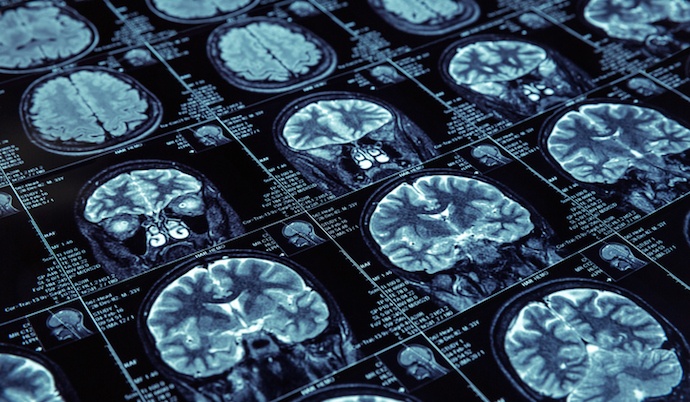

AI đang ngày càng được ứng dụng vào những lĩnh vực rất phức tạp mà tưởng chừng chỉ dành cho những bộ năo kiệt xuất của loài người, tiêu biểu chính là y học. Ảnh: IoT For All.

Theo Vox, thời điểm đó phát biểu của Pichai vấp phải sự hoài nghi lớn. Nhưng gần 5 năm sau, lời tiên đoán dần trở thành hiện thực. AI đang ngày càng được ứng dụng vào những lĩnh vực rất phức tạp mà tưởng chừng chỉ dành cho những bộ năo kiệt xuất của loài người, tiêu biểu chính là y học.

Từ những h́nh ảnh đen trắng về ảnh chụp MRI của một người bị ung thư tuyến tiền liệt, chương tŕnh AI đă phân tích hàng ngh́n h́nh ảnh trong số đó để làm mẫu dữ liệu.

Họ tạo ra thuật toán cho mô h́nh AI bằng cách sử dụng hàng ngh́n nghiên cứu MRI, một số từ những người bị chẩn đoán mắc bệnh ung thư tuyến tiền liệt và c̣n lại là những bệnh nhân khỏe mạnh.

Các bác sĩ tạo ra thuật toán cho mô h́nh AI bằng cách sử dụng hàng ngh́n nghiên cứu MRI. Ảnh: American Brain Foundation.